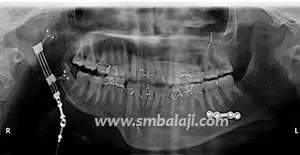

The goal of treatment in hemifacial microsomia is to elongate the deficient jaw bone to restore facial symmetry and correct the slanting bite (occlusion). To achieve this, an advanced and effective treatment technique is distraction osteogenesis. This is a new technique for regenerating new bone by slow, progressive stretching of the bone, without requiring a bone graft.

The jaw bone on the deficient side is cut. A sophisticated device called distractor is placed such that the two arms of the device are fixed to the two segments of jaw bone. After a few days, a screw attached to the distractor is turned gradually, ideally at a rate of 1 mm per day. When this is done, the two cut segments move apart and new bone is formed in the resultant gap. After the new bone is stabilized, the distractor device is removed.

Subsequently, the jaw bone is lengthened to the desired amount correcting the asymmetry of the face. This is a powerful tissue engineering technique for generating unlimited bone.

Eminent Facio-Maxillary Surgeon Dr. S.M. Balaji is highly acclaimed for his prowess in the treatment of Hemifacial Microsomia. He is a pioneering expert in this field and has applied several revolutionary techniques including “Simultaneous Maxillary and Mandibular Distraction” giving excellent results to set right facial asymmetry.